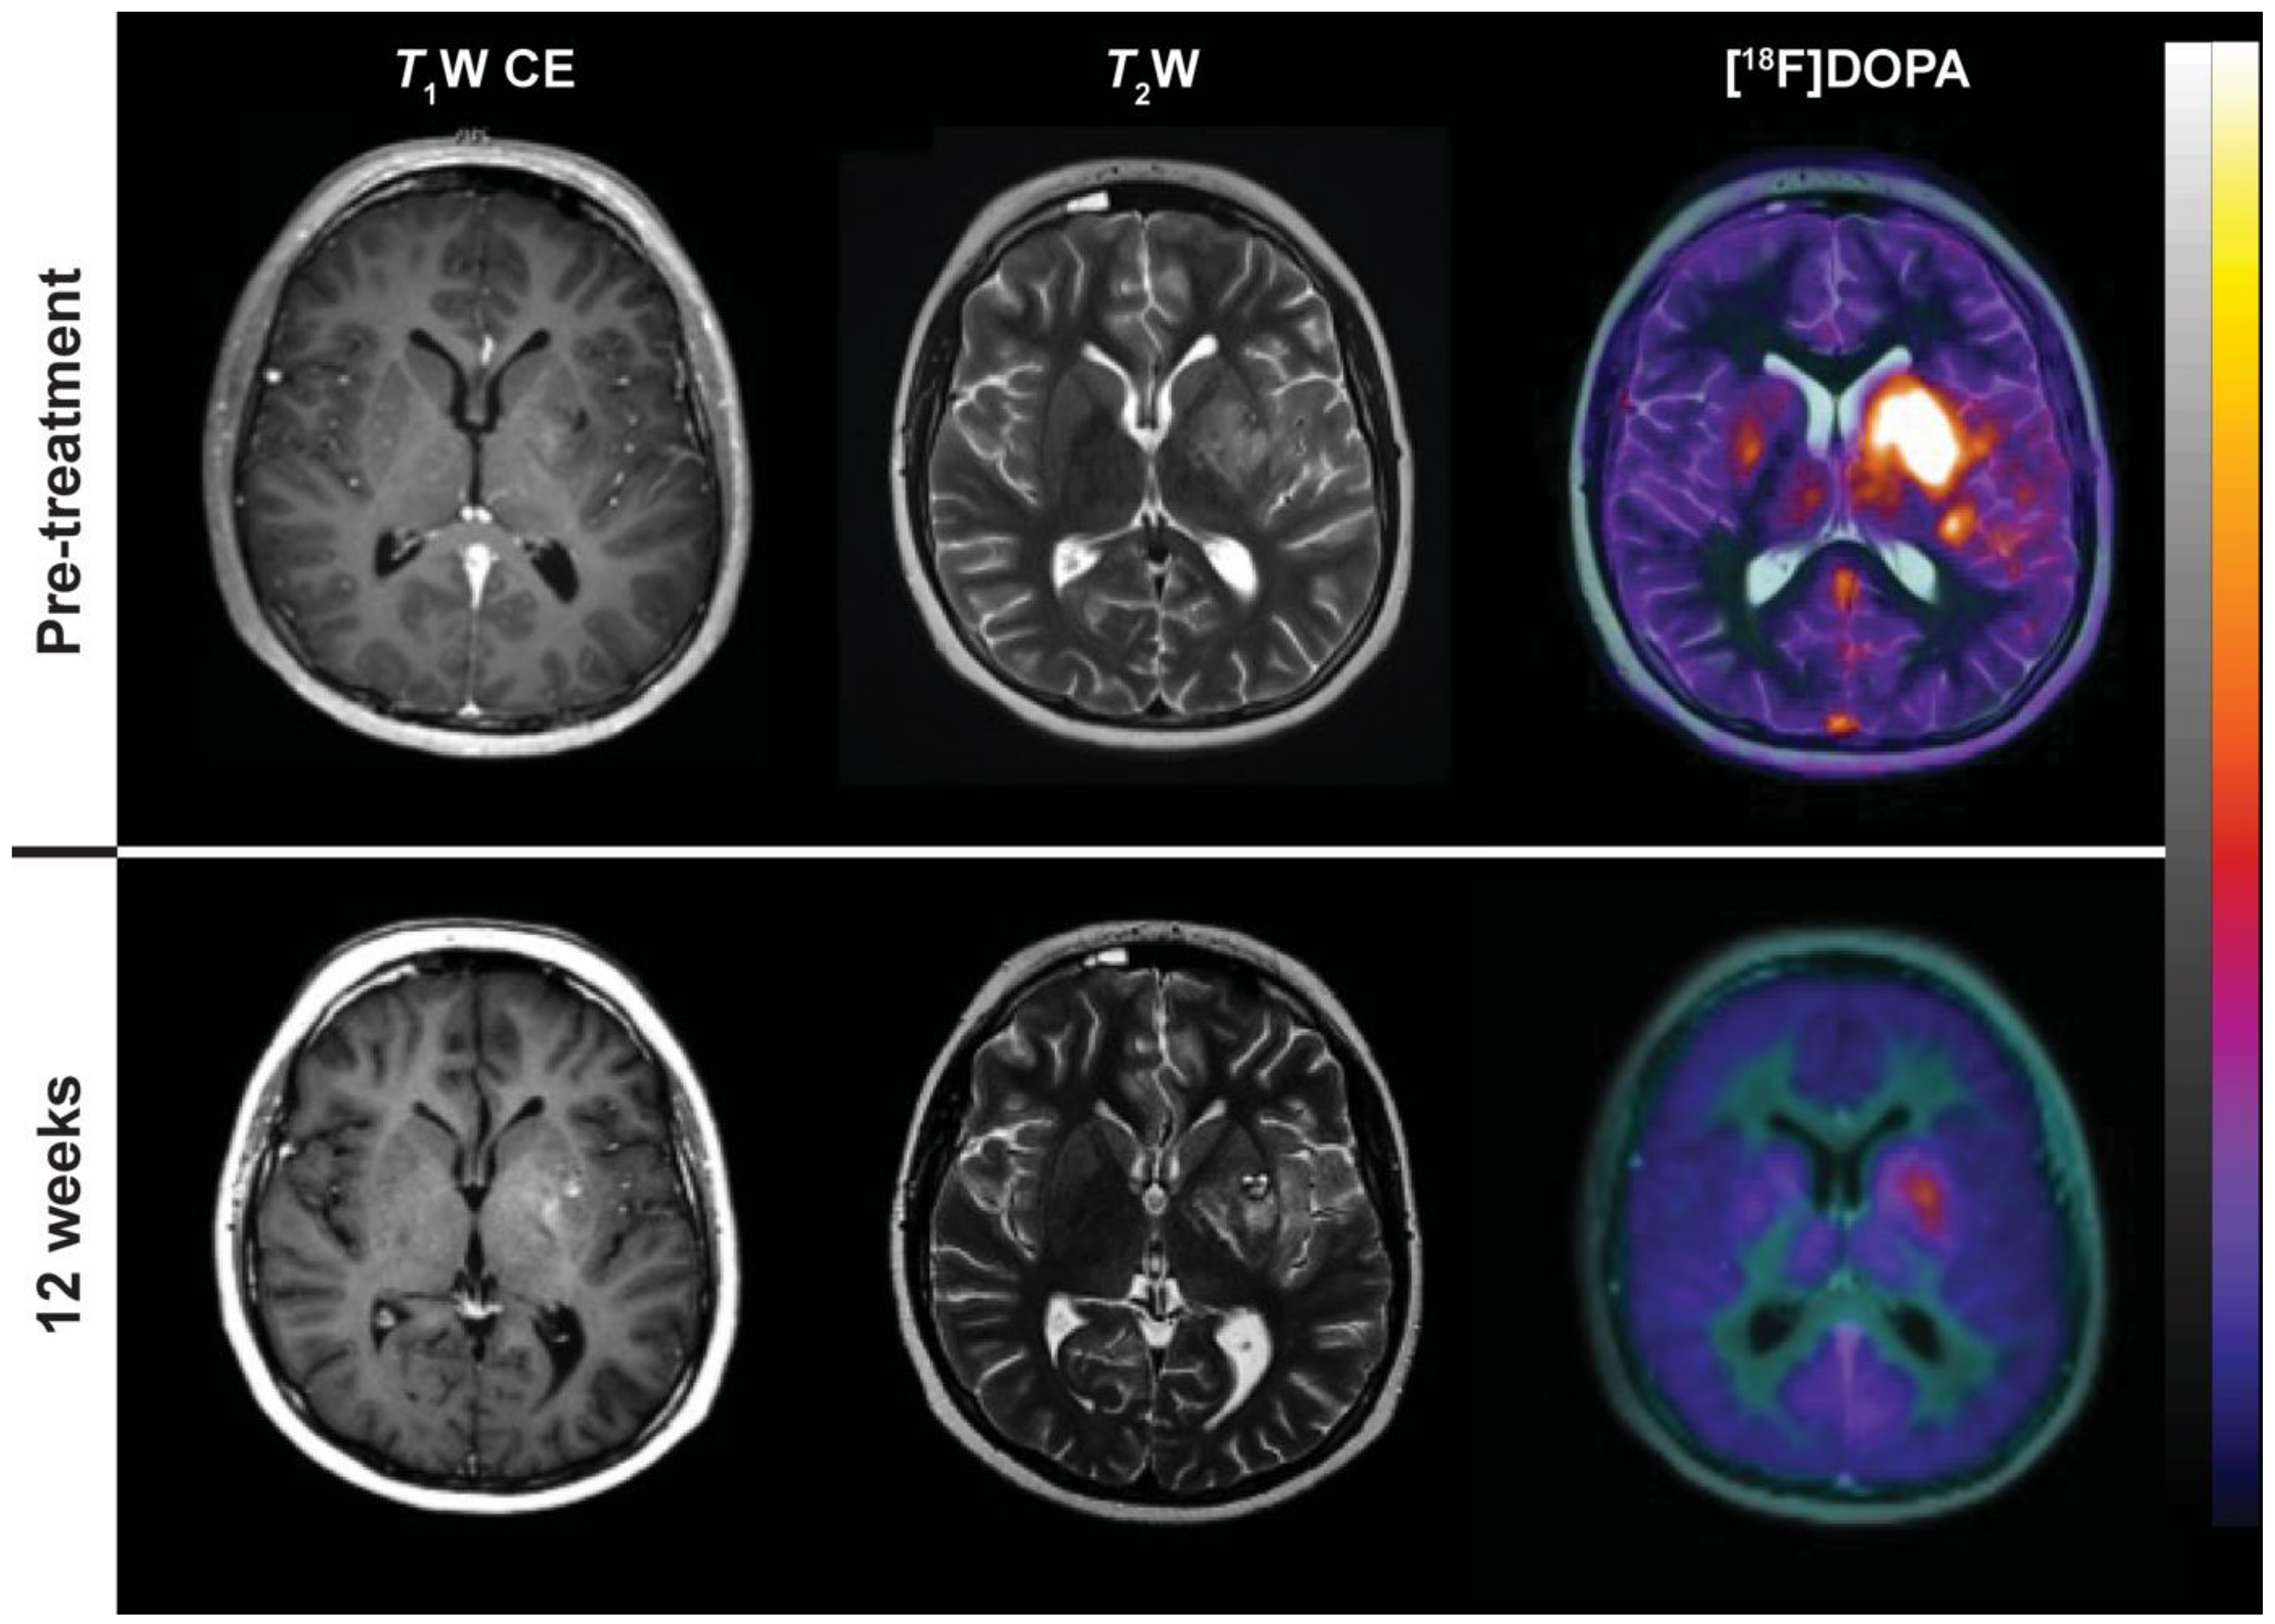

7.3. PET Imaging of Brain Tumours

- Galldiks, N.; Langen, K.J.; Holy, R.; Pinkawa, M.; Stoffels, G.; Nolte, K.W.; Kaiser, H.J.; Filss, C.P.; Fink, G.R.; Coenen, H.H.; et al. Assessment of treatment response in patients with glioblastoma using O-(2-18F-fluoroethyl)-L-tyrosine PET in comparison to MRI. J. Nucl. Med. 2012, 53, 1048–1057. [Google Scholar] [CrossRef] [PubMed]

- Cicone, F.; Minniti, G.; Romano, A.; Papa, A.; Scaringi, C.; Tavanti, F.; Bozzao, A.; Maurizi Enrici, R.; Scopinaro, F. Accuracy of F-DOPA PET and perfusion-MRI for differentiating radionecrotic from progressive brain metastases after radiosurgery. Eur. J. Nucl. Med. Mol. Imaging 2015, 42, 103–111. [Google Scholar] [CrossRef] [PubMed]